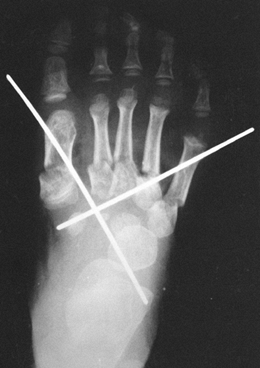

incompletely corrected clubfoot reveal inadequate dorsiflexion of the

os calcis or parallelism of the talar and calcaneal axes.

Anteroposterior (AP) views show medial deviation of the first

metatarsal axis relative to the talar axis, a function of subluxation

of the talonavicular joint (the navicular ossification center itself

does not appear for several years, and its position must be inferred);

the axes of the talus and calcaneus likewise become parallel because

the external rotation of the subtalar joint is lost. Most of the angles

described for evaluation of clubfoot are based on radiographs of older

children, and they date from an era when treatment was nonoperative and

involved prolonged casting. We have not found radiographs to be helpful

in determining which children should have early surgery; the decision

is made more easily on clinical grounds.